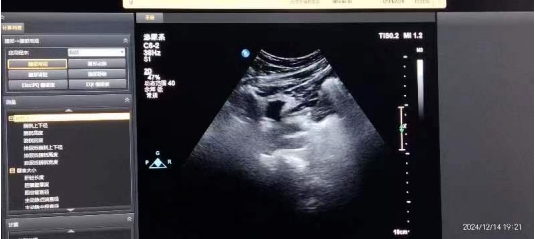

體外沖擊波碎石,利用超聲定位,將沖擊波精準(zhǔn)作用到腎或輸尿管結(jié)石處,在不停地“擊打”下,結(jié)石便會(huì)層層剝離,最終變?yōu)榉勰?。其?yōu)點(diǎn)包括創(chuàng)傷小、恢復(fù)快、操作方便、無(wú)需麻醉、費(fèi)用低,對(duì)于結(jié)石較小且無(wú)其他嚴(yán)重全身疾患的患者,在門(mén)診就可進(jìn)行治療。